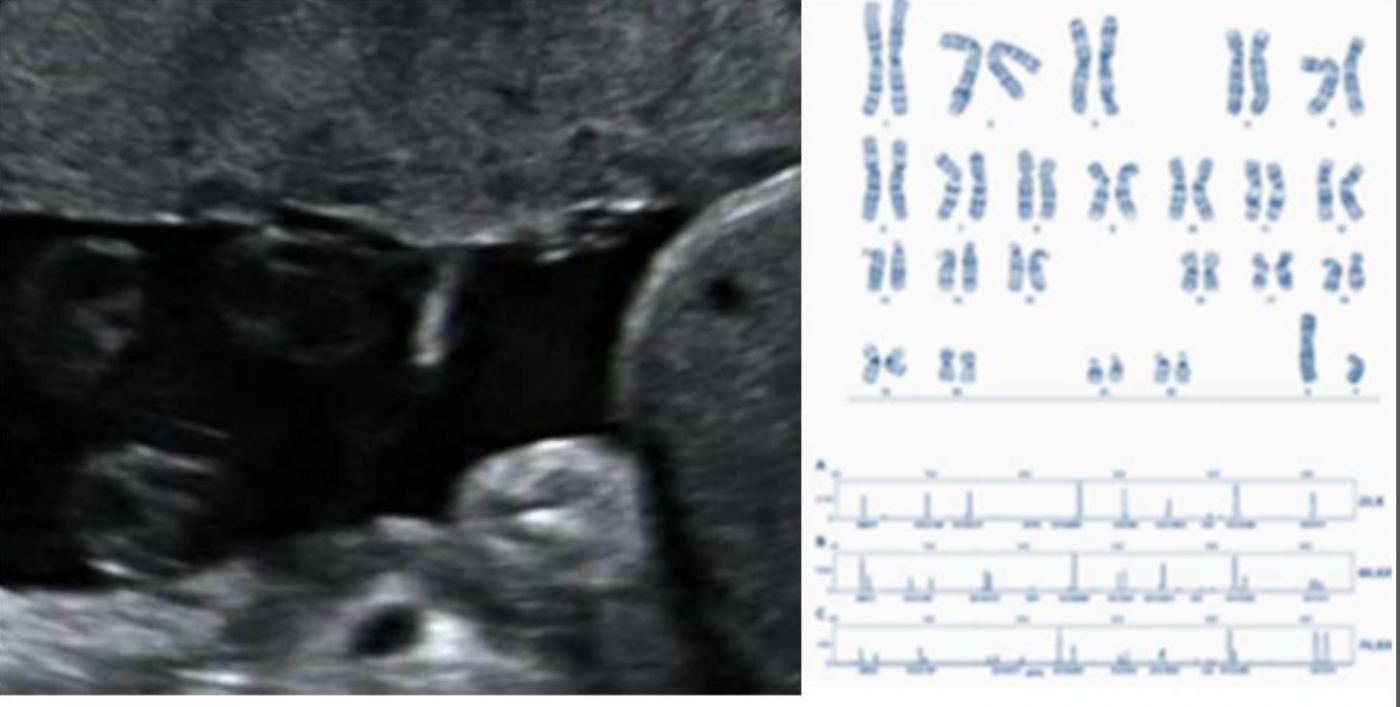

Dra. Ma Àngels Sánchez-Duran. Unitat de Diagnòstic Prenatal. Servei d'Obstetrícia Dra. Irene Valenzuela. Àrea de Genètica Clínica i Molecular Dra. Anna Abulí. Àrea de Genètica Clínica i Molecular Dra. Carlota Rodó. Unitat de Medicina Fetal. Servei d'Obstetrícia Dra. Alba Farràs. Unitat d'Ecografia Obstètrica. Unitat d'Innovació en Obstetrícia. Servei d'Obstetrícia